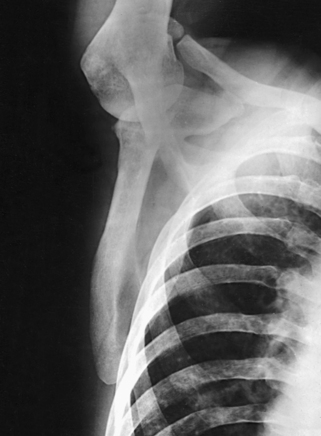

This projection, described by Rubin et al.,1 obtained its name as a result of the appearance of the scapula. The body of the scapula forms the vertical component of the Y, and the acromion and coracoid processes form the upper limbs. This projection is useful in the evaluation of suspected shoulder dislocations.

Structures shown: The scapular Y is shown on an oblique image of the shoulder. In the normal shoulder, the humeral head is directly superimposed over the junction of the Y (Fig. 5-37). In anterior (subcoracoid) dislocations, the humeral head is beneath the coracoid process (Fig. 5-38); in posterior (subacromial) dislocations, it is projected beneath the acromion process. An AP shoulder projection is shown for comparison (Fig. 5-39).

Fig. 5-38 PA oblique shoulder joint showing anterior dislocation (humeral head projected beneath coracoid process).